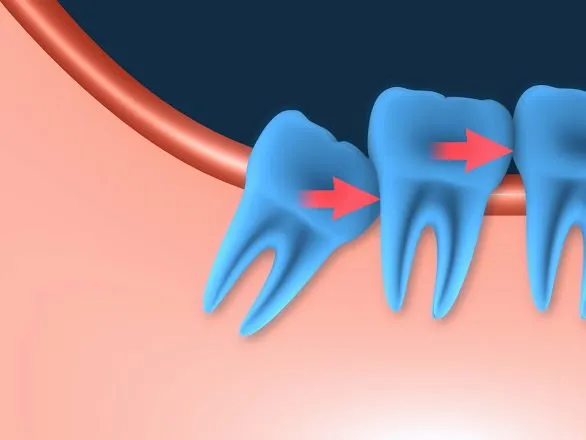

- Posição Incorreta: O siso nasce "deitado" ou inclinado, empurrando os outros dentes.

- O Capuz Gengival: Tecido gengival em cima do dente que funciona como uma armadilha de sujeira.

- Dificuldade de Acesso: Falta de espaço na boca para que a escova e o fio dental cheguem ao local.